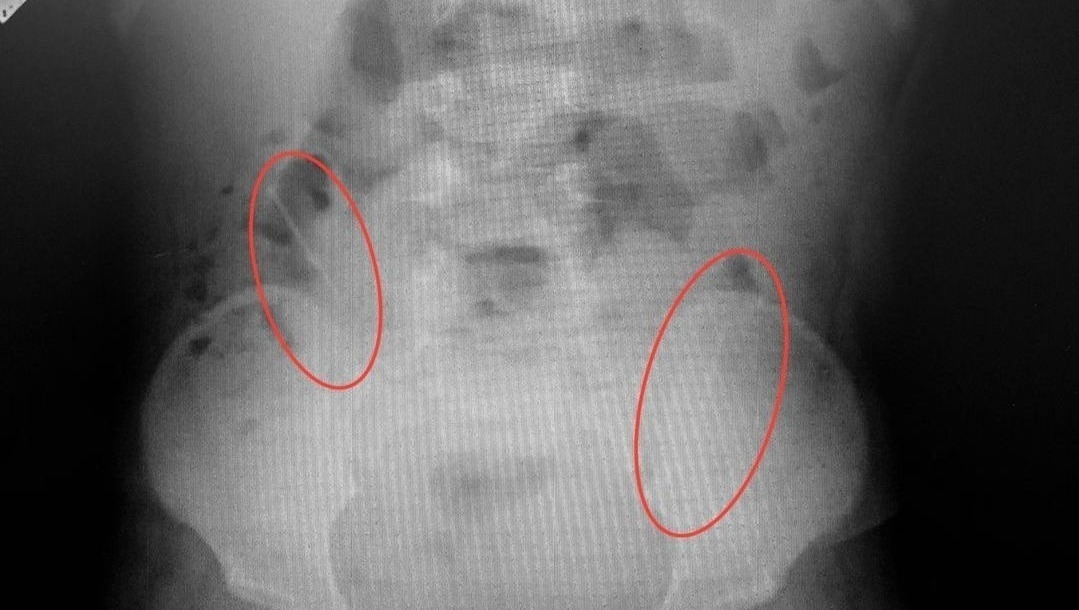

В апреле в уфимскую детскую клиническую больницу № 17 поступил семилетний мальчик, который проглотил шарики от магнитного конструктора. При рентгенографии желудочно-кишечного тракта были выявлены две тени округлой формы, соединенные между собой диаметром 5 мм, предположительно, в куполе слепой кишки. Хирургическая бригада провела экстренную операцию: магнитные шарики были успешно извлечены. Врачи использовали менее травматичный оперативный метод: не вскрывая просвет кишечника, при помощи пальцев переместили инородные тела в червеобразный отросток и провели аппендэктомию. Если бы магниты оказались в разных петлях кишечника, то произошла бы перфорация кишечника и каловый перитонит, что очень опасно для жизни.